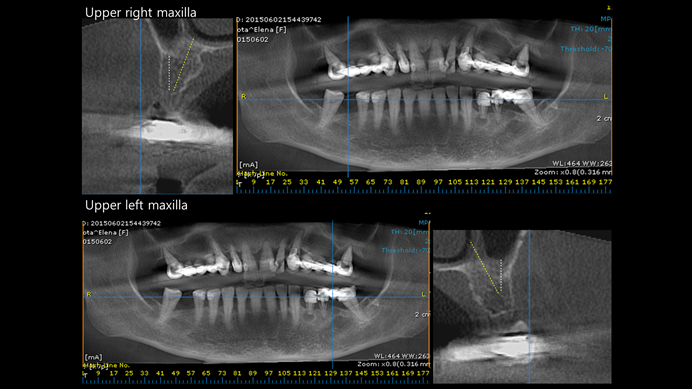

Clinical case: Extraction of all teeth in upper maxilla,

immediate implant placement, & provisionalization

- Courtesy of Dr. Iulian Filipov, Romania -

Keywords

AnyRidge, immediate placement, immediate provisionalization, maxillary fully edentulous case, initial stability, edentulous, Dr. Iulian Filipov, R2GATE, MEGA ISQ

Products:

AnyRidge implant system, Mega ISQ, R2GATE

“AnyRidge ensures long-term biological stability

& functionality even in

full-mouth rehabilitation case. ”